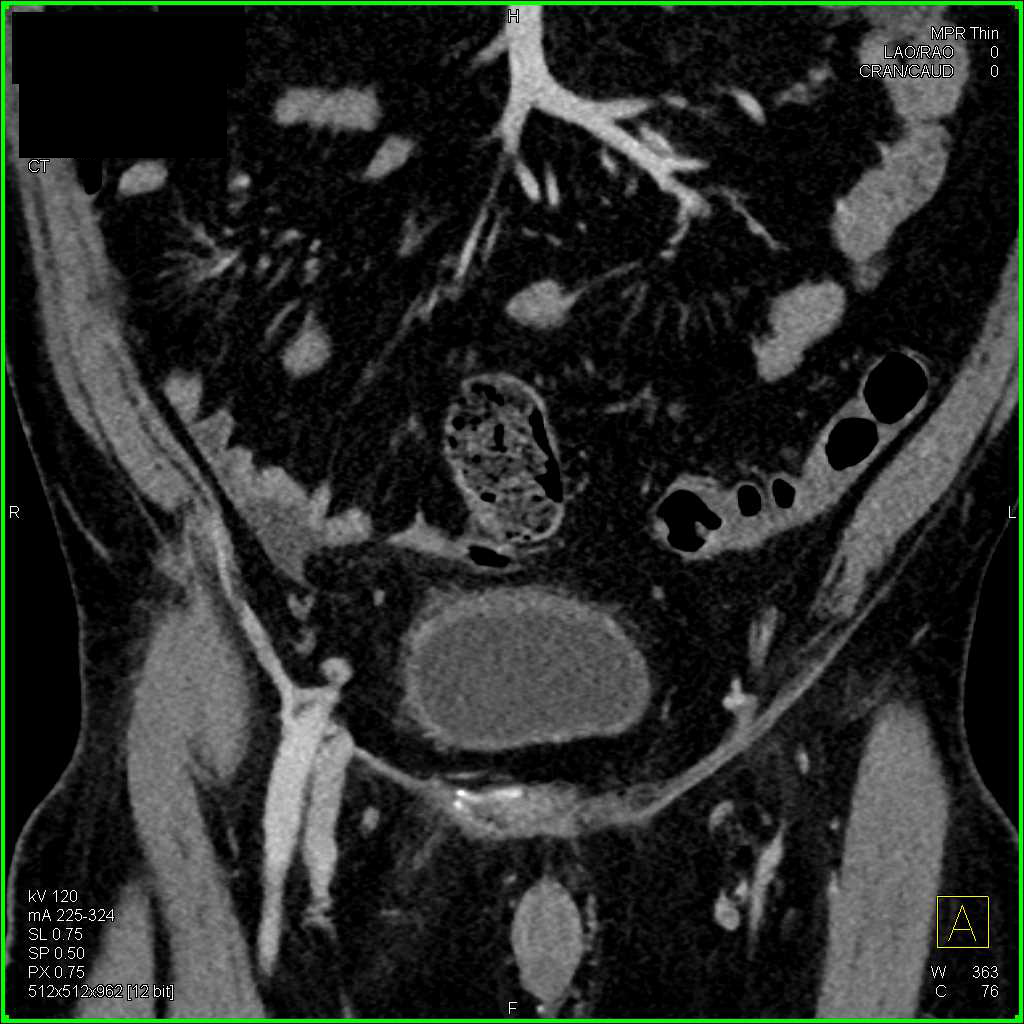

Extensive Adenopathy from Renal Cell Carcinoma